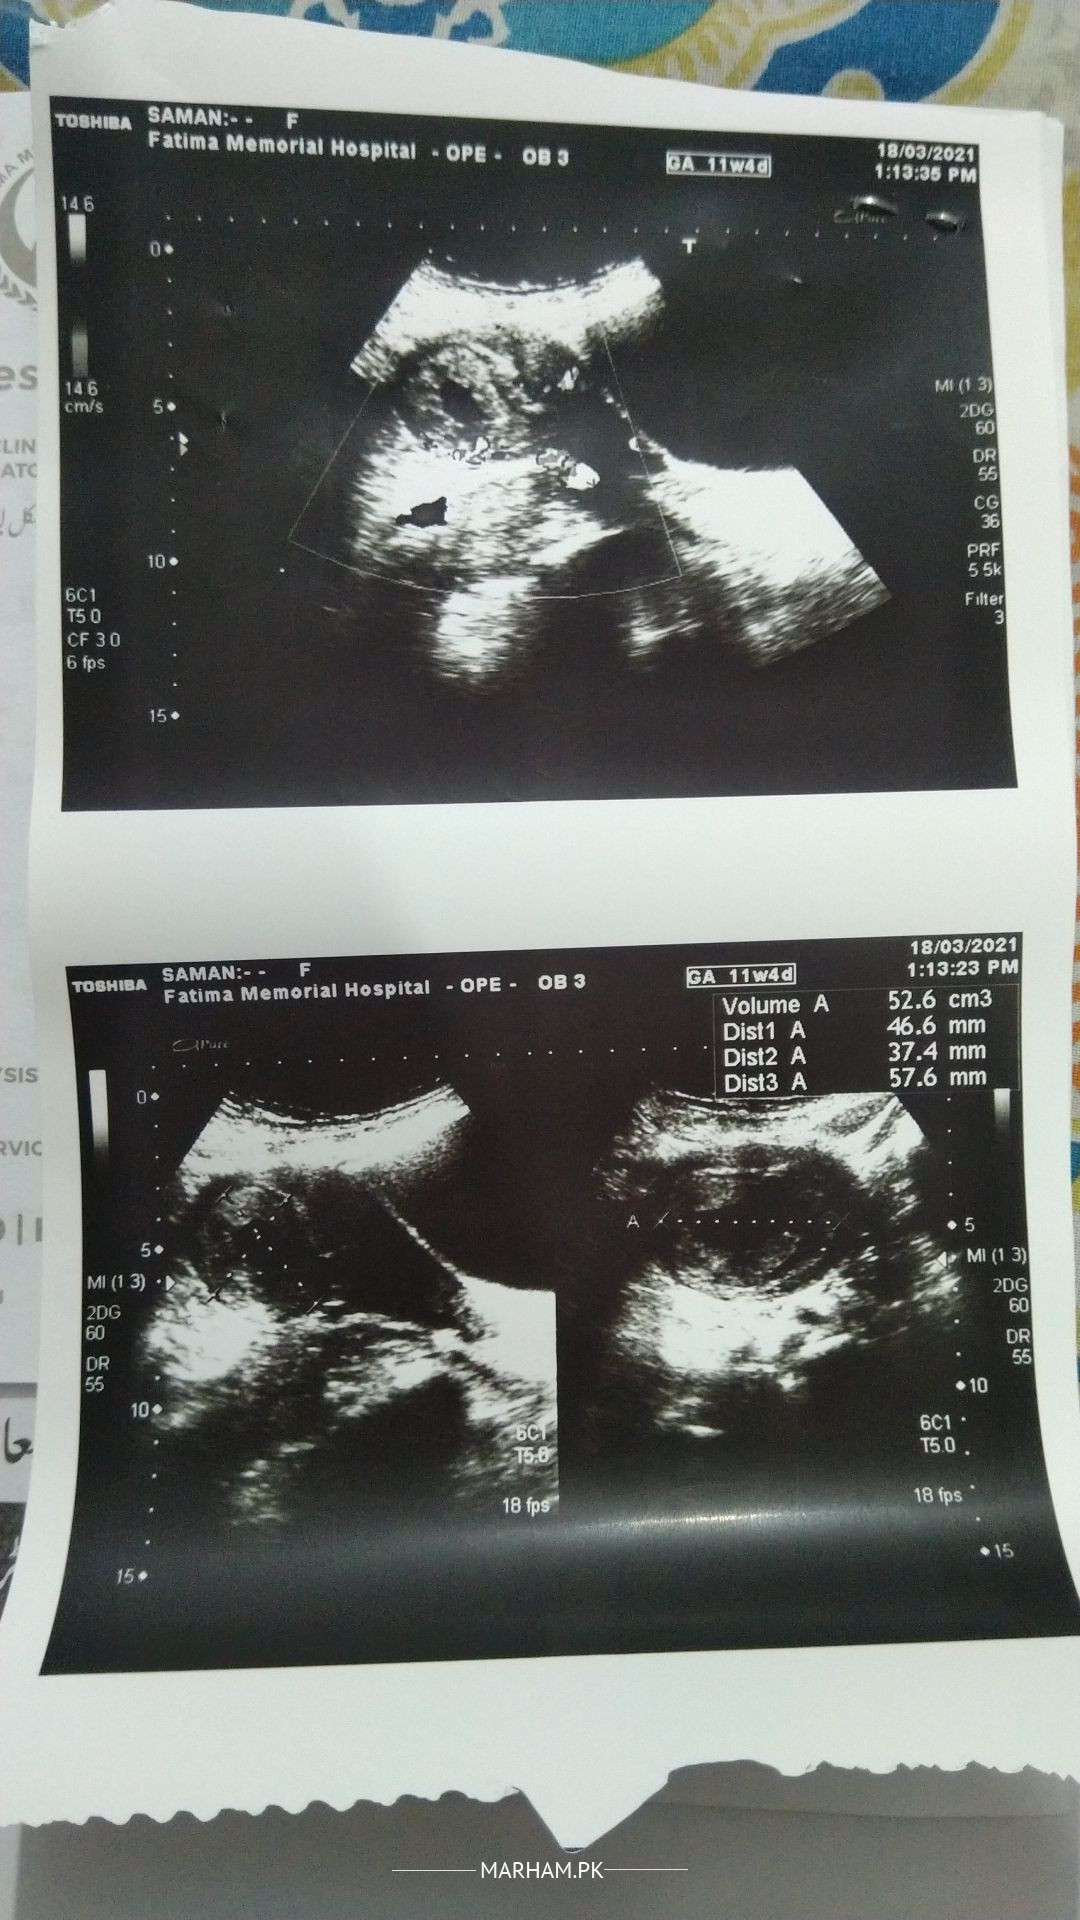

Assalam o alaikumThis report does not suggest missed miscarriage. Please get examined for decision regarding management.